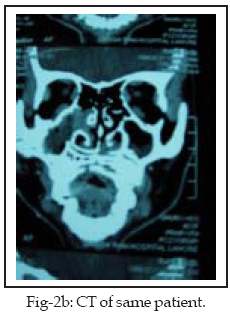

Maxillary sinus, frontal sinus, ethmoids and sphenoid sinus were involved, in descending order of frequency; maxilla was the most commonly affected. Five patients were diagnosed as having acute osteomyelitis (35%); an equal number were diagnosed as having chronic osteomyelitis of which one had a fistula on the cheek (Fig-1) and one had fistula due to tuberculosis (Fig-2ab).

Odontogenic infections and chronic sinusitis each gave rise to osteomyelitis in two cases (10%) of the patients with osteomyelitis of the palate and maxilla combined of which one case had a fistula in the hard palate (Fig-3). Chronic sinusitis was the main cause of frontal bone osteomyelitis in two cases (10%), one of which had a discharging fistula in left frontal bone displacing the eye ball.